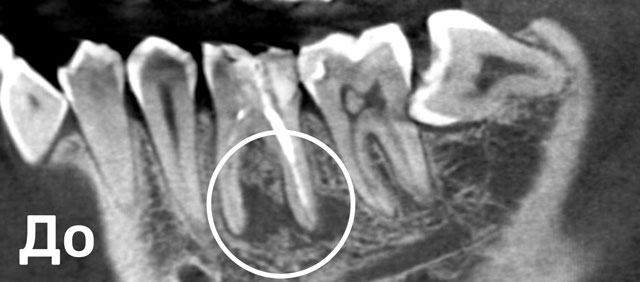

Перелечивали зуб с Марией Александровной после некачественного первичного лечения у другого врача. Образовалась киста + недобросовестный доктор оставил часть инструмента в канале. Очень понравилось то, Еще... что доставали часть забытого инструмента (и в общем все процедуры проводились) под микроскопом. Не было паники, что что-то повредится. Было всё абсолютно безболезненно. После всех процедур, через 2 месяца пришла на повторный снимок, киста практически ушла. Динамика хорошая. Безумно благодарна Марии Александровне за проделанную работу. За здоровыми и красивыми зубками – теперь только к ней!

До